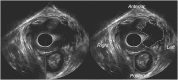

Total pelvic floor ultrasound is used for the dynamic assessment of pelvic floor dysfunction and allows multicompartmental anatomical and functional assessment. Pelvic floor dysfunction includes defaecatory, urinary and sexual dysfunction, pelvic organ prolapse and pain. It is common, increasingly recognized and associated with increasing age and multiparity. Other options for assessment include defaecation proctography and defaecation MRI. Total pelvic floor ultrasound is a cheap, safe, imaging tool, which may be performed as a first-line investigation in outpatients. It allows dynamic assessment of the entire pelvic floor, essential for treatment planning for females who often have multiple diagnoses where treatment should address all aspects of dysfunction to yield optimal results. Transvaginal scanning using a rotating single crystal probe provides sagittal views of bladder neck support anteriorly. Posterior transvaginal ultrasound may reveal rectocoele, enterocoele or intussusception whilst bearing down. The vaginal probe is also used to acquire a 360° cross-sectional image to allow anatomical visualization of the pelvic floor and provides information regarding levator plate integrity and pelvic organ alignment. Dynamic transperineal ultrasound using a conventional curved array probe provides a global view of the anterior, middle and posterior compartments and may show cystocoele, enterocoele, sigmoidocoele or rectocoele. This pictorial review provides an atlas of normal and pathological images required for global pelvic floor assessment in females presenting with defaecatory dysfunction. Total pelvic floor ultrasound may be used with complementary endoanal ultrasound to assess the sphincter complex, but this is beyond the scope of this review.